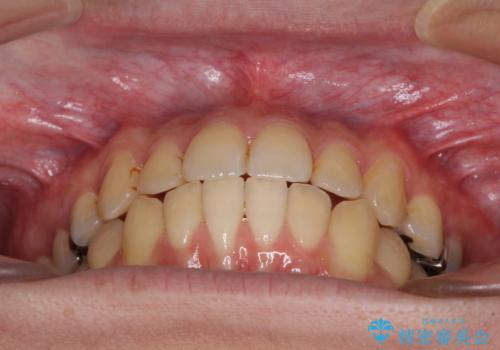

前歯のクロスバイトをインビザラインで矯正治療

- 前歯のデコボコとクロスバイトを気にして来院された患者様です。

前歯を早く整えたいとの希望があったので、ワイヤー矯正にて短期間でクロスバイトを解消し、その後インビザラインにて整えることとしました。